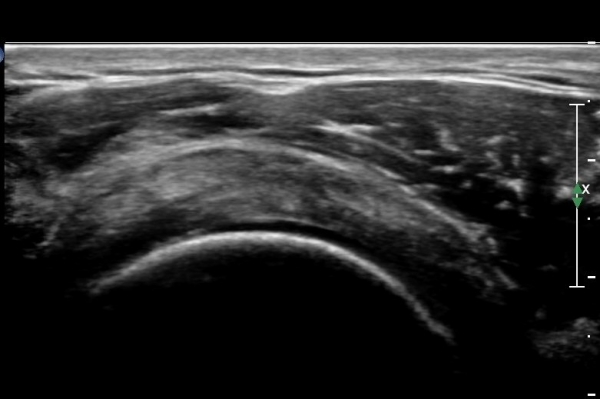

ȸÀü±Ù°³°£°Ý(rotator cuff interval)  Ⱦ´Ü¸é°Ë»ç¿¡¼­ ±¹»ó°Ç ³»ÃøÀÇ °Ç ¶Ñ²²°¡ ¾ã¾ÆÁø °ÍÀ¸·Î

º¸¿© ±Ø»ó°Ç ³»Ãø ºÎºÐÆÄ¿©¸ª ¾Ï½ÃÇÔ(»çÁø 3, ).